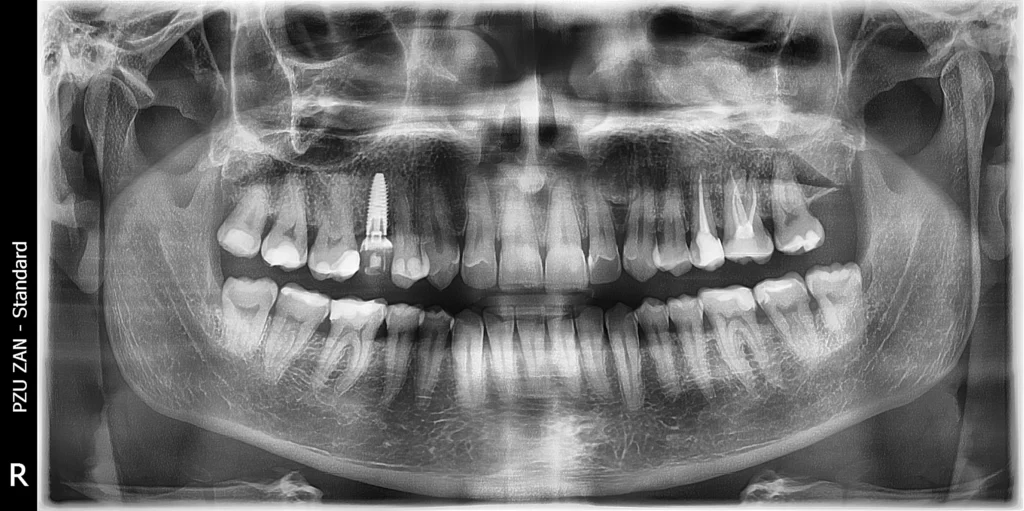

We began with detailed CBCT 3D imaging and careful digital planning. This allowed us to map out the exact position, angle, and depth of the implant before the procedure even began.

Using a computer-aided surgical guide, we performed a precise extraction and immediately placed the implant in the ideal position. Right after the intervention, the patient was provided with a temporary tooth, maintaining both appearance and comfort during the healing phase.

After a healing period of six months, the implant achieved excellent osseointegration. At this stage, we proceeded with the final restoration phase, ensuring everything was perfectly stable and ready.

We delivered a high-quality, screw-retained zirconia crown that blends seamlessly with the natural teeth. The result is a subtle yet powerful transformation—a small change that made a big difference in the patient’s smile and confidence.Â